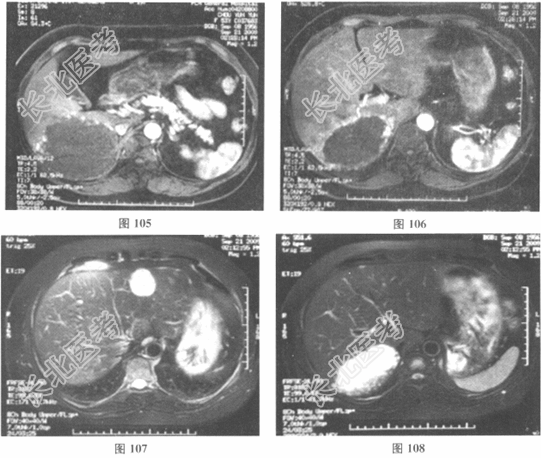

- 多项选择题2.[提示] 该患者增强CT和MRI检查提示肝脏有多发病变,其中右后叶的占位病灶约9.8cm×6.2cm×5cm大小; 结果见图101~图108。

请问该患者的临床诊断应考虑( ) A、右后叶肝恶性淋巴瘤

B、右后叶肝海绵状血管瘤

E、右后叶血管肉瘤

F、肝血管内皮细胞瘤

G、右后叶FNH